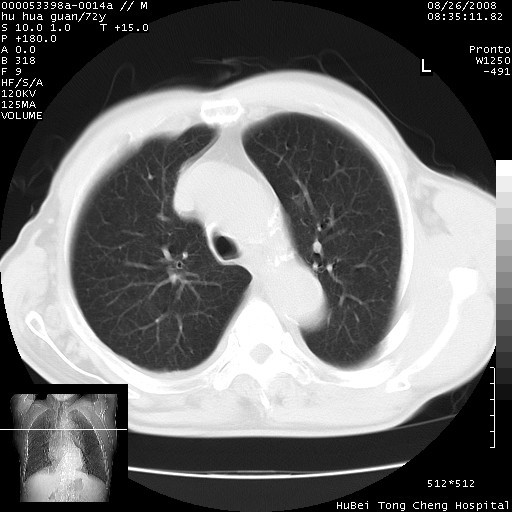

标题: CT15582:M,72Y。请老师帮分析胸部病变。

可以明确的说。肯定不是主动脉夹层破裂出血!考虑为淋巴瘤或间叶组织来源的恶性肿瘤可能性大。右肺小结节建议薄层观察,如能发现恶性征象,那椎前改变就考虑为转移所致。至于双侧少量胸水乃静脉血回流受阻所致。

1、右上肺结节病变,肺泡癌不除外,请随诊;左下肺近后纵隔病变,考虑纵隔型肺癌侵犯大血管可能;

2、右下肺背段少许炎症,双侧胸腔积液,右下肺纤维索条。

降主动脉前移位,后纵隔占位

后纵隔占位,降主动脉前移位;双侧胸腔积液;应排外食管病变侵犯血管可能;